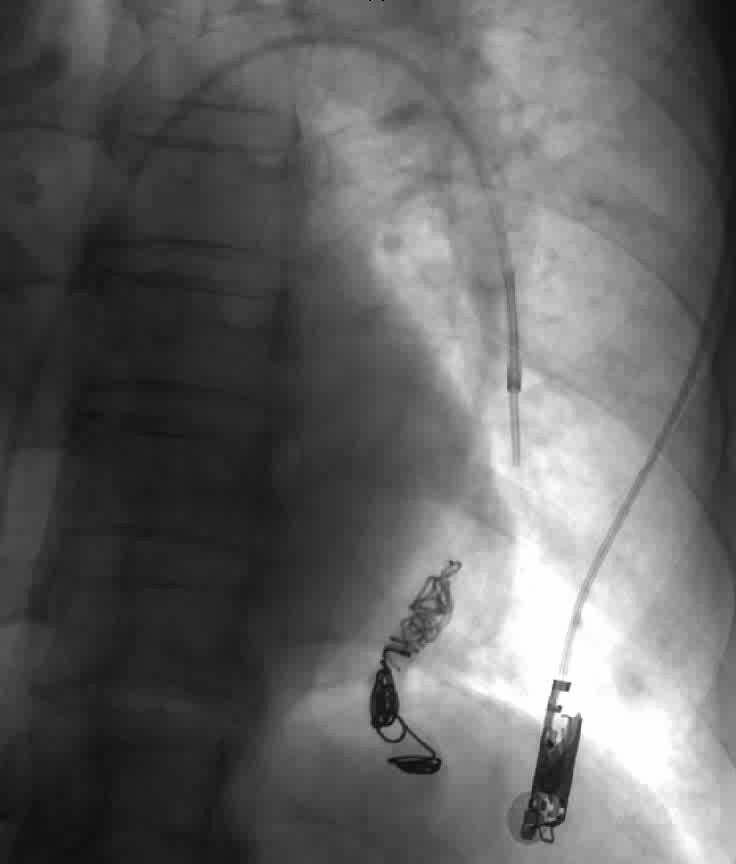

Four sessions of embolization therapy were performed by radiologist in Princess Margaret Hospital from May 2011 to Nov 2011. Antibiotic prophylaxis was given before each session to prevent cerebral abscess. Echocardiogram was also arranged after each session of embolization therapy. So far, findings were quite similar to her pre-procedure ones and no pulmonary hypertension was demonstrated. With successful embolization therapy, she was able to gradually tail down and eventually wean off oxygen supplement with room air SpO2 93-95% afterwards. Follow-up computer tomography scan was arranged 6-12 months after the last embolization for monitoring in addition to regular outpatient visit.

Nowadays, embolization therapy is the first line treatment for PAVM. It has replaced invasive surgery since 1980s. The aim of treatment is mainly to prevent neurological complications secondary to paradoxic embolism and improve hypoxemia. By deploying detachable ballons, coils or amplatzers to the aneurysmal part of PAVM, right-to-left shunting is disrupted. The efficacy of embolization therapy had been repeatedly demonstrated by clinical trials with success rate up to 80-97%1,4,5,6,7,8. It is a safe procedure. Self-limiting pleuritic chest pain and fever are the most common complications. Rarely, it can cause air embolism, stroke, migration of coils etc9. Pulmonary hypertension after embolization therapy was reported but study suggested most patients, in fact, had a fall instead of raised pulmonary artery pressure afterwards10. So far, there is no international consensus regarding the absolute contra-indications of performing embolization therapy. But investigators believe that in those patients with pre-existing moderate to severe pulmonary hypertension and positive balloon occlusion test (defined as rise more than 5 mmHg in mean pulmonary arterial pressure), risks outweigh potential benefits11,12,13.

Figure 3: embolization therapy and patient’s latest chest X-rays after total 4 sessions of procedures